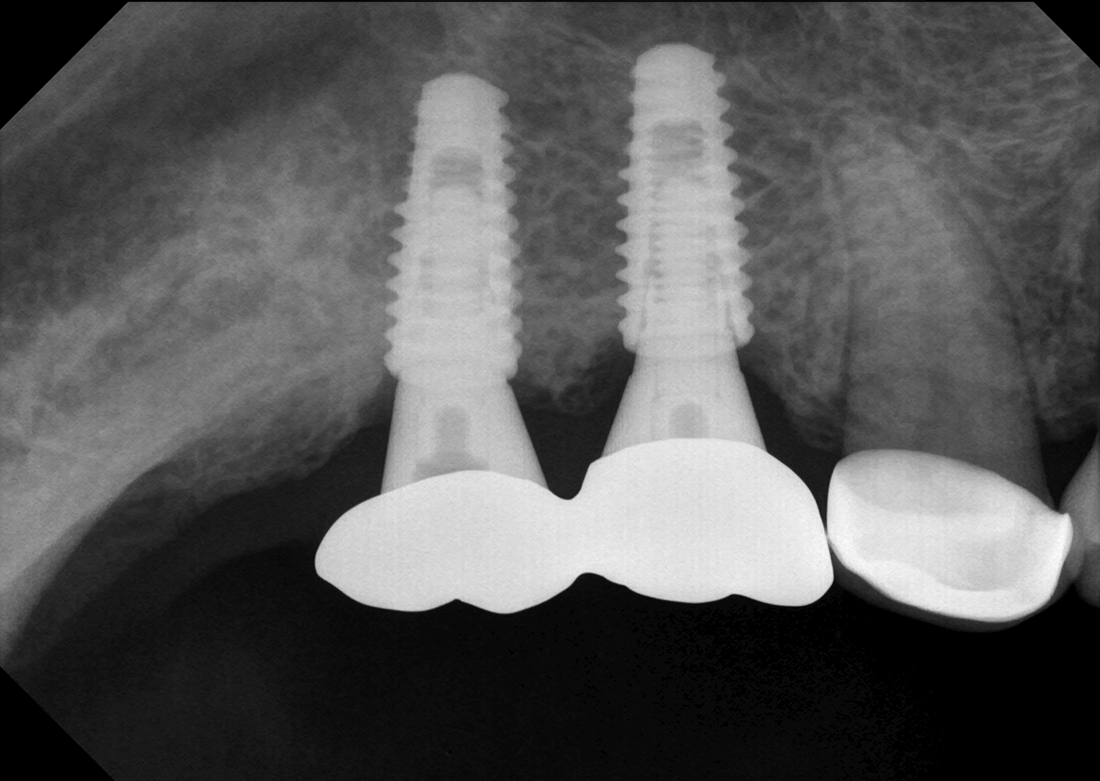

KLİNİK FOTOĞRAFLAR

Firmanın uzun yıllara dayanan dental görüntüleme tecrübesi ile son teknoloji sensor reseptörleri kullanılarak üretilmiştir ve görüntü kalitesi mükemmel düzeydedir.